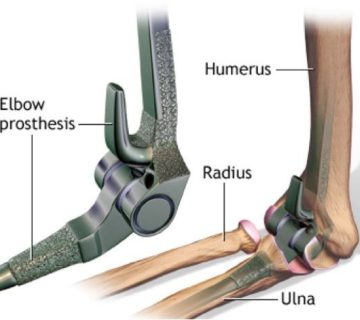

- بی حرکتی آرنج و مچ دست بسیار اهمیت دارد .

- مچ دست مجددا کاملاً بی حرکت می شود اما خم شدن و باز شدن آرنج باید شروع شود.

- خم شدن و بازشدن آرنج ادامه می یابد، اما از چرخش ساعد اجتناب می شود.